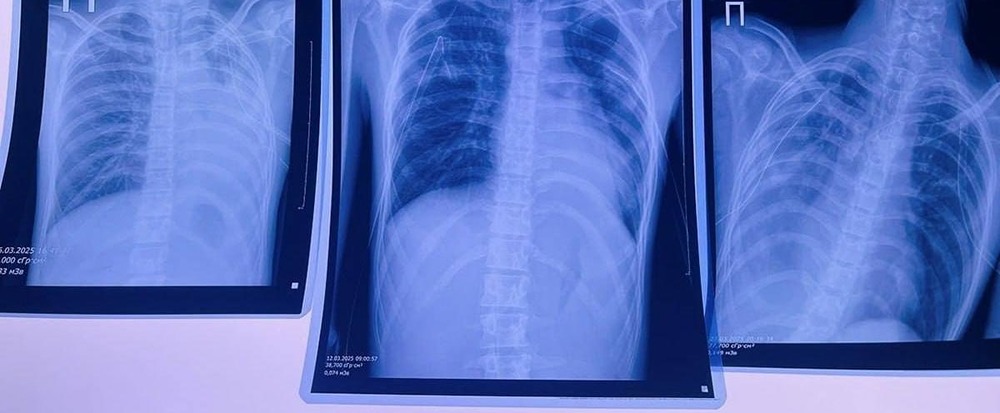

В Кировской области произошло трагическое происшествие, связанное с использованием электронных сигарет. Одна из пострадавших — 16-летняя девушка, которая начала курить вейп около трёх лет назад. В прошлом году у неё появились кашель и гнойная мокрота. Сейчас она находится в больнице с диагнозом двусторонняя бронхопневмония. Другой подросток из Кирова также использовал электронные сигареты на протяжении нескольких лет. В результате у него произошло повреждение лёгких, и он был госпитализирован в реанимацию.